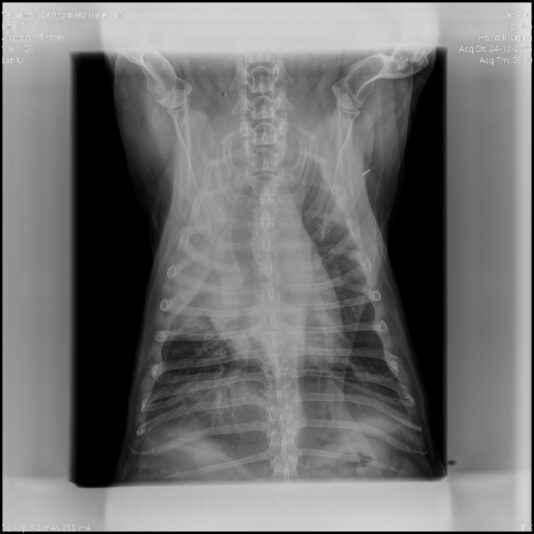

beoordeling RX thorax bij hoestende hond

Graag zou ik jullie hulp willen vragen over de volgende patient: Het is een kruising jack russel met franse bulldog van 15 jaar oud, Mk. Hij is 4 weken plots begonnen met hoesten. Het is een droge piepende hoest, dat vaak eindigt in even kokhalzen. Het hoesten is niet gekoppeld aan activiteit, maar in diepe slaap hoest hij niet. Eetlust…